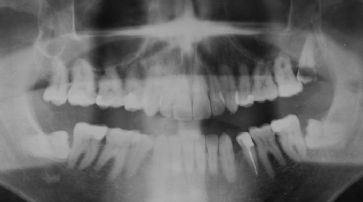

Häufiges Röntgen beim Zahnarzt kann schaden

Washington - Regelmässige Röntgenaufnahmen beim Zahnarzt können die Gefahr für gewisse Hirntumoren erhöhen. Für die Studie werteten US-Wissenschaftler die Daten von fast 1500 Meningiom-Patienten im Alter von 20 bis 79 Jahren aus.

Demnach liegt bei Patienten, denen mindestens einmal jährlich die Zähne geröntgt wurden, die Wahrscheinlichkeit für einen solchen Hirntumor um 1,4 Mal bis dreimal höher als bei Vergleichspersonen ohne regelmässige Röntgenaufnahmen. Dies berichteten die Forscher am Dienstag im Fachblatt «Cancer».

Röntgenaufnahmen beim Zahnarzt sollten nur wenn nötig vorgenommen werden. /

Studienleiterin Elizabeth Claus von der Universität Yale zufolge ist die höhere Tumorgefahr je nach Art der Röntgenaufnahmen und dem Alter der Betroffenen unterschiedlich. Insgesamt werde durch die Studie aber unterstrichen, dass mit Röntgenaufnahmen auch beim Zahnarzt verantwortlich umgegangen werden müsse. Laut den Richtlinien der US-Zahngesellschaft soll bei Kindern mindestens einmal alle zwei Jahre eine Röntgenaufnahme von den Zähnen gemacht werden, bei Erwachsenen alle zwei oder drei Jahre.